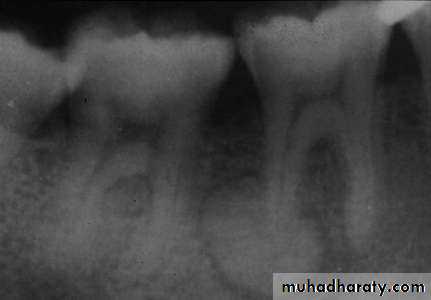

• Cementoblastoma

• Radiography:• Typically appears as radio opaque rounded mass with thin radiolucent margin.

• Attached to the root.

• Resorption of the related root is common.